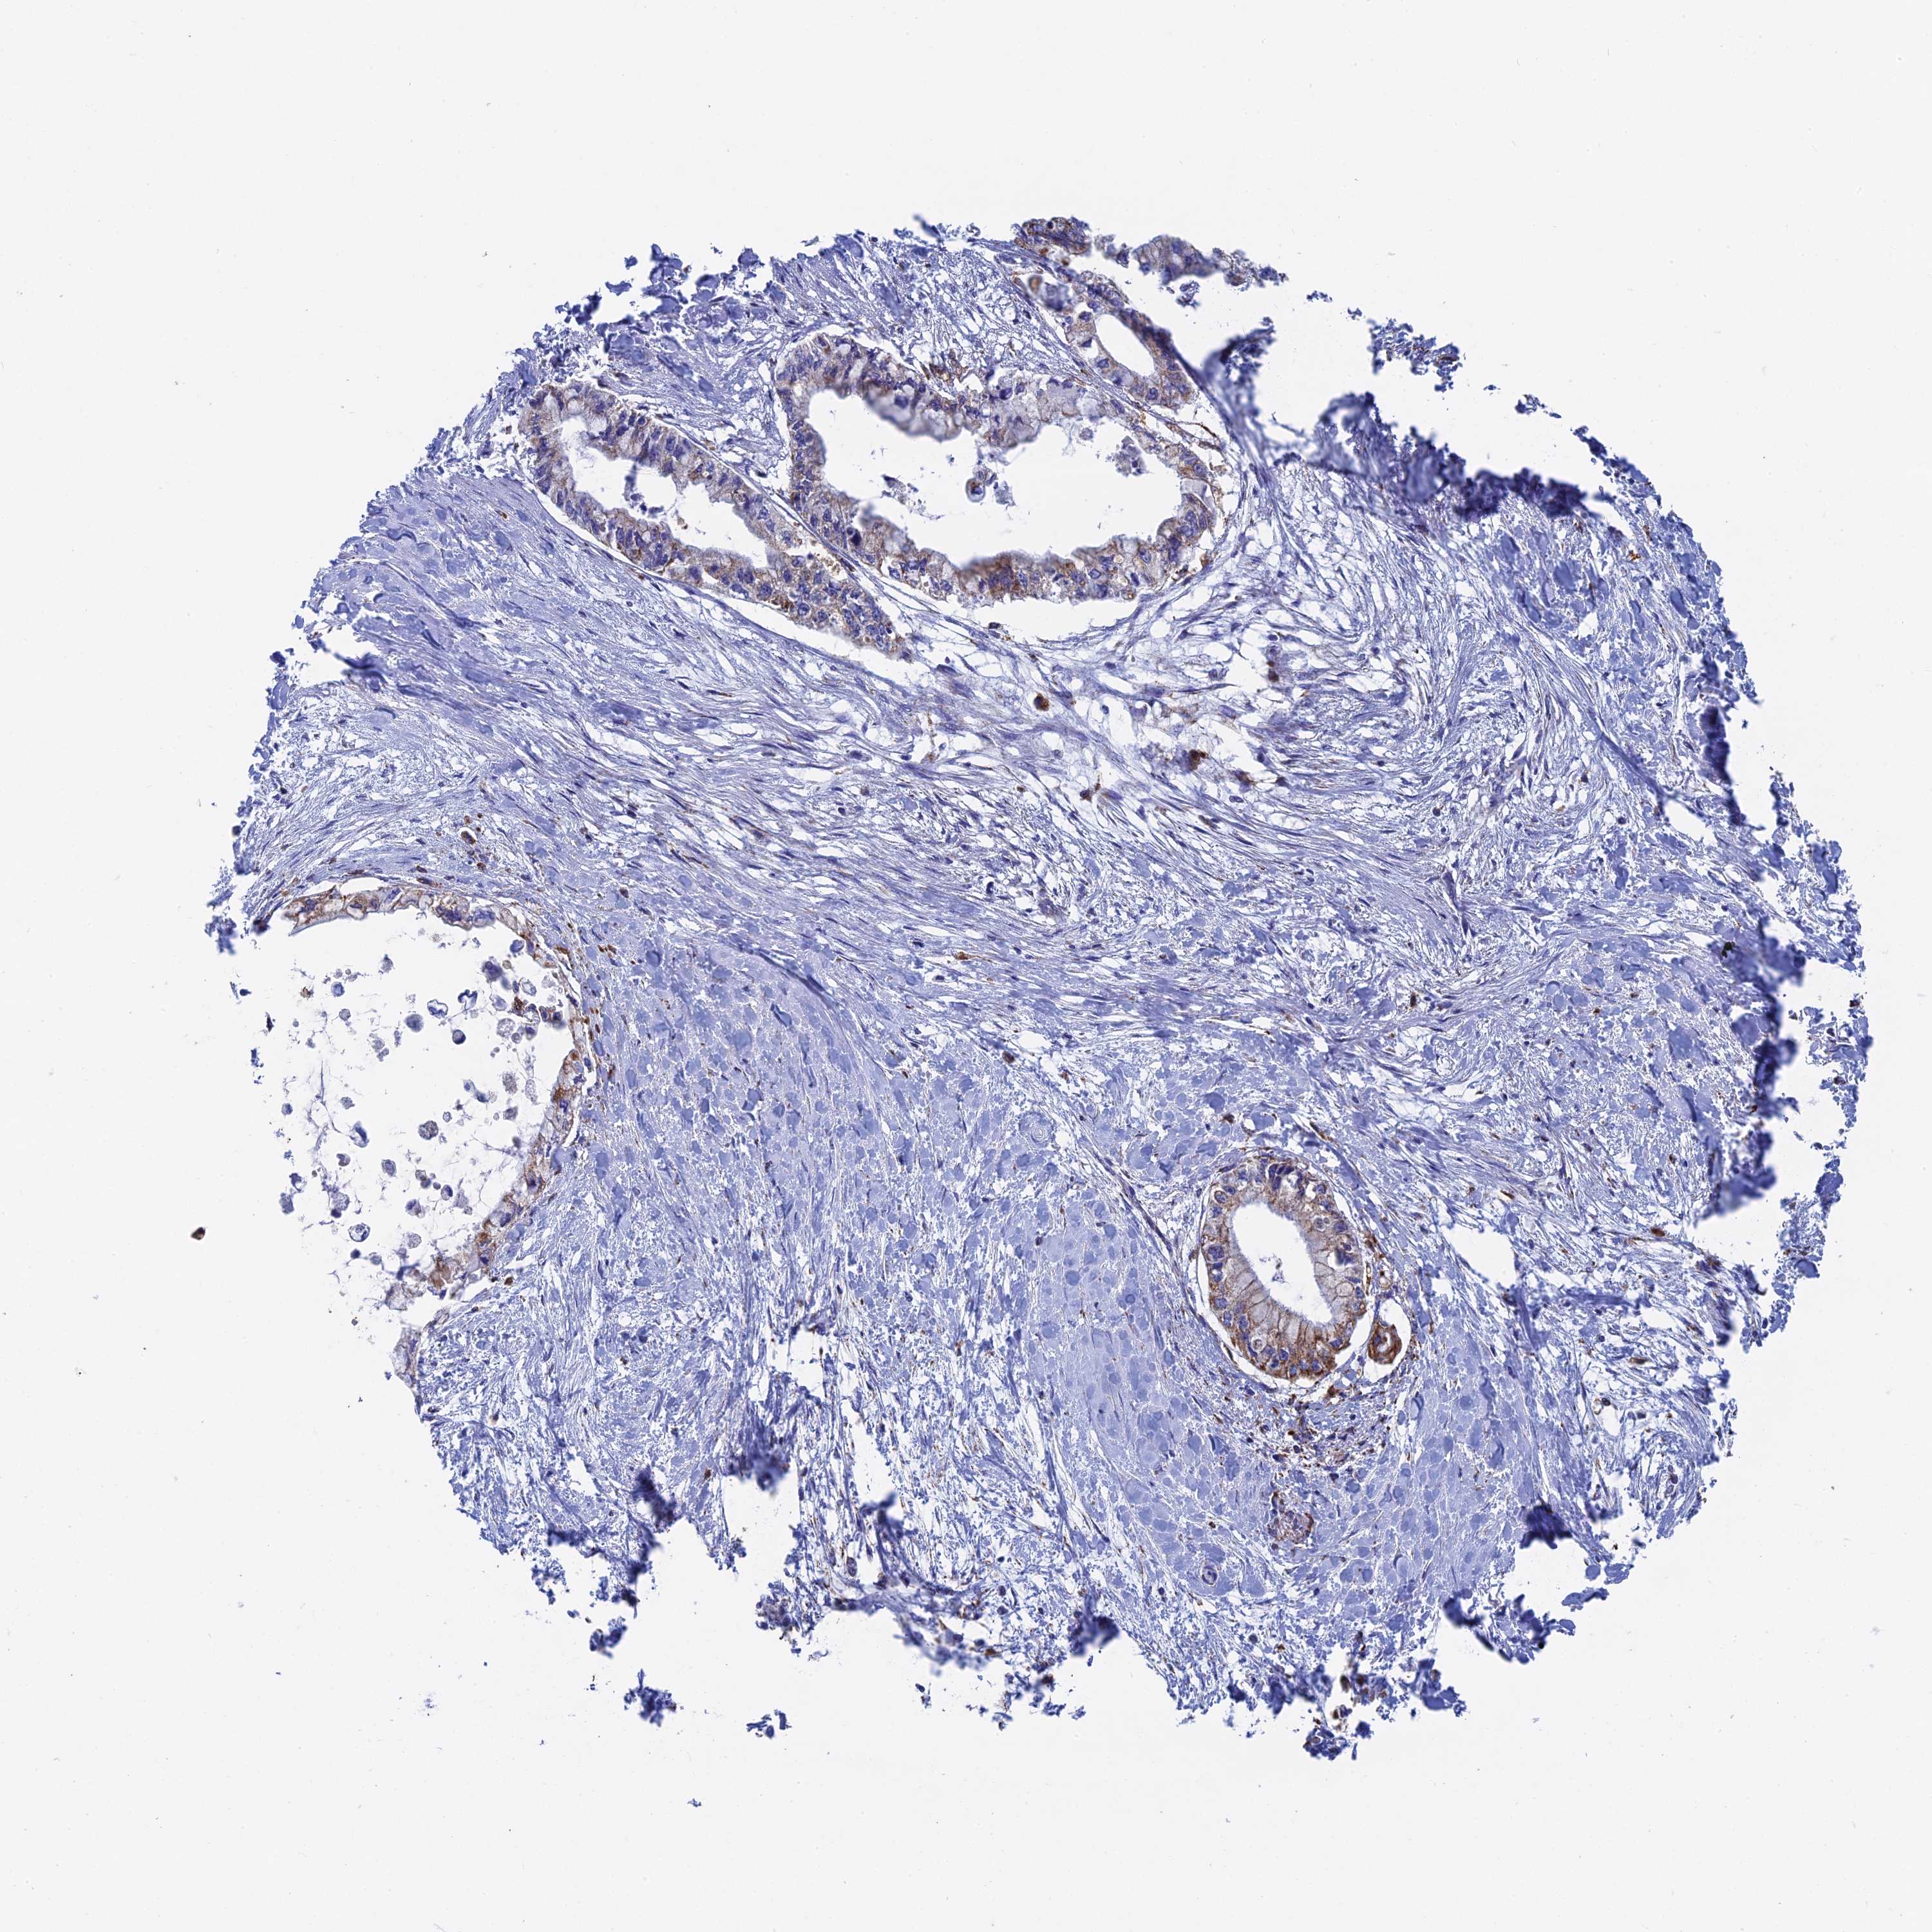

PANCREATIC CANCER - Protein expressioni

A mouse-over function shows sample information and annotation data. Click on an image to view it in a full screen mode. Samples can be filtered based on level of antibody staining by selecting one or several of the following categories: high, medium, low and not detected. The assay and annotation is described here.

Note that samples used for immunohistochemistry by the Human Protein Atlas do not correspond to samples in the TCGA dataset.

Antibody stainingi

Antibody staining in the annotated cell types in the current human tissue is reported as not detected, low, medium, or high, based on conventional immunohistochemistry profiling in selected tissues. This score is based on the combination of the staining intensity and fraction of stained cells.

Each image is clickable and will lead to virtual microscopy that enables deeper exploration of all samples and also displays staining intensity scores, fraction scores and subcellular localization as well as patient and tissue information for each sample.

Antibody HPA041626

Staining

High

Medium

Low

Not detected

Intensity

Strong

Moderate

Weak

Negative

Quantity

>75%

75%-25%

<25%

None

Location

Nuclear

Cytoplasmic/membranous

Cytoplasmic/membranous,nuclear

Adenocarcinoma, NOS